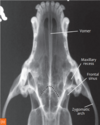

12

Q

Review normal anatomy.

A

How well did you know this?

13

Review normal VD/DV anatomy.